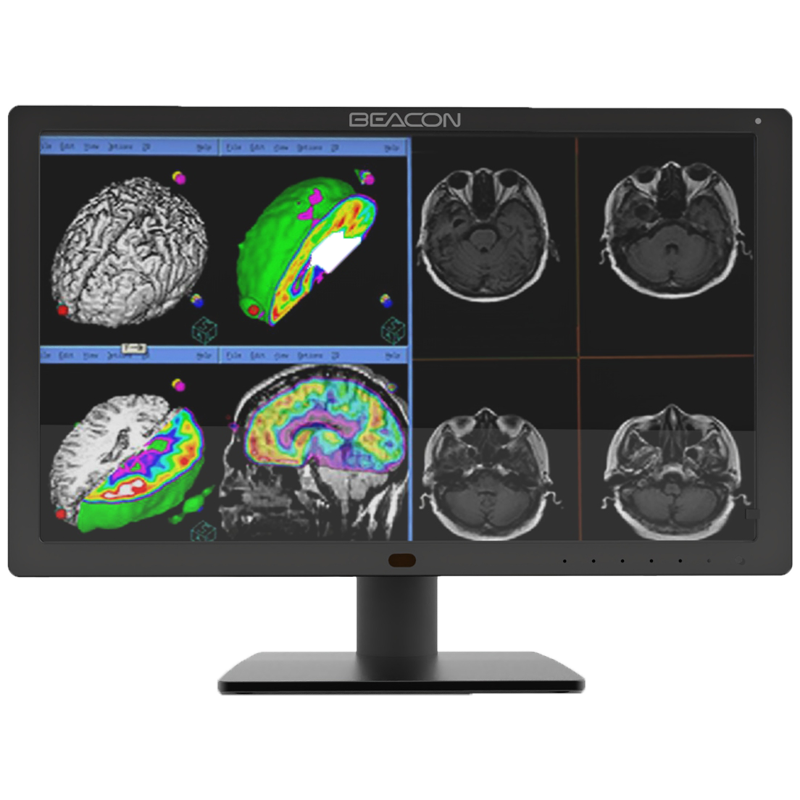

C510S tiene funciones de imagen en color y escala de grises, 5 millones de píxeles de resolución ultra alta, brillo ultra alto, contraste ultra alto, amplio ángulo de visión y bajo consumo de energía. Puede ser ampliamente utilizado en varios equipos de imágenes médicas incluyendo mama digital y sistema de PACS.

Las imágenes médicas, incluyendo los detalles más sutiles, se pueden visualizar con precisión. Mantener la coherencia de visualización entre diferentes pantallas, así como la visualización y las diferentes modalidades de imágenes, garantizar la precisión del diagnóstico.

Pantalla de diagnóstico

Pantalla de diagnóstico